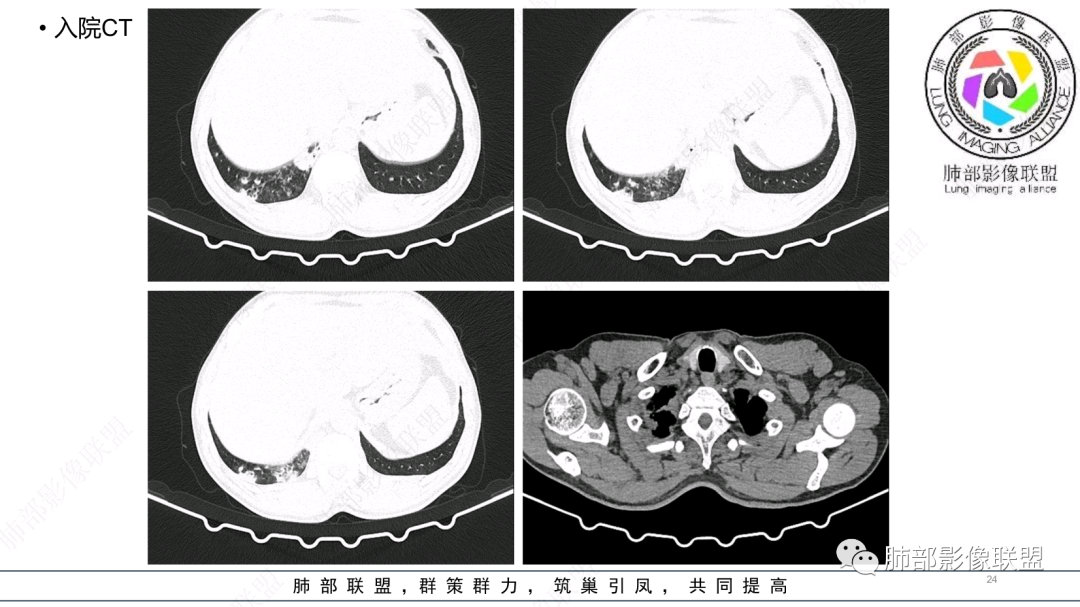

56岁,工作性质:环卫工人。主诉:咳、痰、喘、发病一周。急性起病(或者慢病+AE),呼吸道感染症状。化验指标白细胞、中性、CRP明显升高。影像学显示多灶性,有柱状支扩,囊状支扩等结构肺病,责任细菌主要考虑铜绿假单胞菌,不排除合并其他细菌以阴杆为主;存在树芽影,发热,炎症沿支气管束分布,是否合并TB?真菌?;树芽伴发热支原体感染也要需要考虑进去;全肺多灶性炎症,部分病灶周围有晕,右上叶疑似反晕,内部疑似有丝,右下肺考虑存在粘液栓,加之环卫工工作性质,考虑霉菌,主要考虑曲霉。

影像改变为支扩伴气道来源感染,部分实变性伴有小脓肿及钙化,结合PCT及白细胞、中性粒明显增高,符合细菌感染,首先考虑奴卡,绿脓次之,因为临床有喘息、影像实变性有钙化,加上环卫工这一职业史,需要鉴别曲霉或奴卡合并曲霉。

CT:双肺延支气管血管束分布斑片状、团块状、树芽状密度增高影,部分边界模糊,支气管扩张、部分管壁增厚。考虑气道吸入细菌性感染,铜绿假单孢?

(3)空洞:因病变是化脓性感染,病灶坏死排出,空洞较常见。          (4)累及胸膜及胸壁可形成胸腔积液、脓胸。